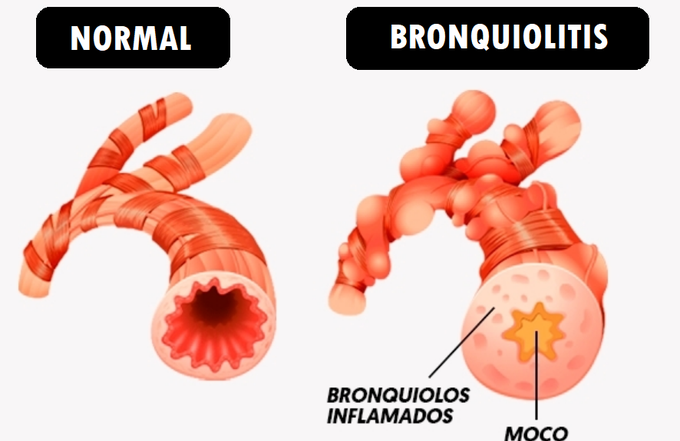

La bronquiolitis es un término que abarca diversos procesos inflamatorios que afectan los bronquiolos, las vías respiratorias más pequeñas con un diámetro de menos de 2 mm. Estos bronquiolos son cruciales para la conducción del aire desde los bronquios más grandes hasta los alvéolos pulmonares, donde ocurre el intercambio gaseoso vital. La inflamación de estos conductos puede ser provocada por diferentes causas y se manifiesta clínicamente de diversas formas.

La bronquiolitis constrictiva se caracteriza por una obstrucción significativa del flujo de aire en los bronquiolos, lo cual conduce a una captura de aire que se evidencia en la espirometría. A menudo, los estudios de radiografía de tórax simples pueden mostrar cambios mínimos, mientras que las tomografías computarizadas revelan obstrucción heterogénea del flujo de aire y captura de aire. Clínicamente, los pacientes con bronquiolitis constrictiva experimentan un curso progresivo y deteriorado debido a la severa limitación en el intercambio gaseoso y la función respiratoria comprometida.